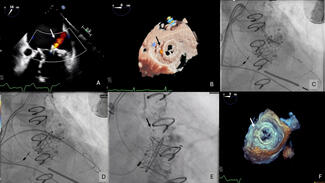

Over 5.7 million people in US and 20 million people worldwide suffer from heart failure and about half of these suffer from Heart Failure with Preserved Ejection Fraction (HFpEF). Most drug trials have shown minimal beneficial effects, and attention has turned to possible device therapy. The CORolla is an elastic device implanted in the LV through transapical approach or percutaneous approach. The device applies direct internal expansion forces distributed on the LV wall and the septum. Clinical studies are in progress. The ImCardia device is an elastic expanding device that is attached to external LV surface through off pump procedure. A study in patients admitted for AVR secondary to aortic stenosis showed trends to improvement in diastolic dysfunction after 24 months.